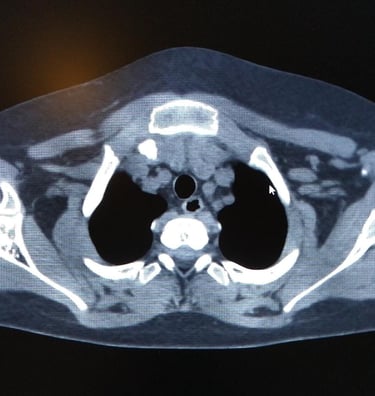

El pectus Carinatum es una malformación en el pecho, donde la pared torácica sobresale hacia fuera, esto ocurre debido a un crecimiento anómalo de los cartílagos costales.

Esta protrusión (proyección hacia delante) hace que el pecho parezca el de un ave, motivo por el cual se le conoce como "pecho de paloma"

Dependiendo de la morfología del paciente, este puede ser tratado mediante la técnica del dr Abramson, que consiste en la colocación de una barra que empuja el esternón hacia adentro.